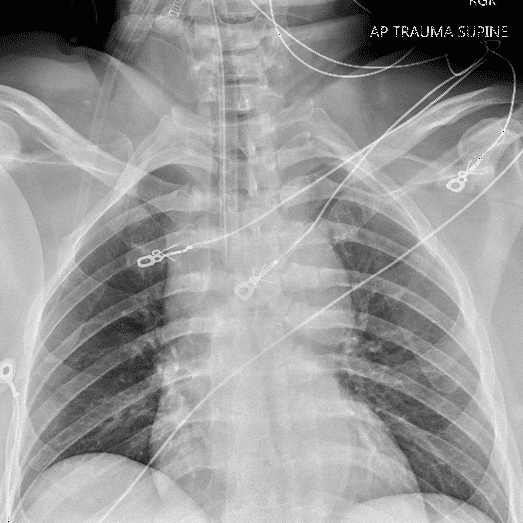

Practice Cases